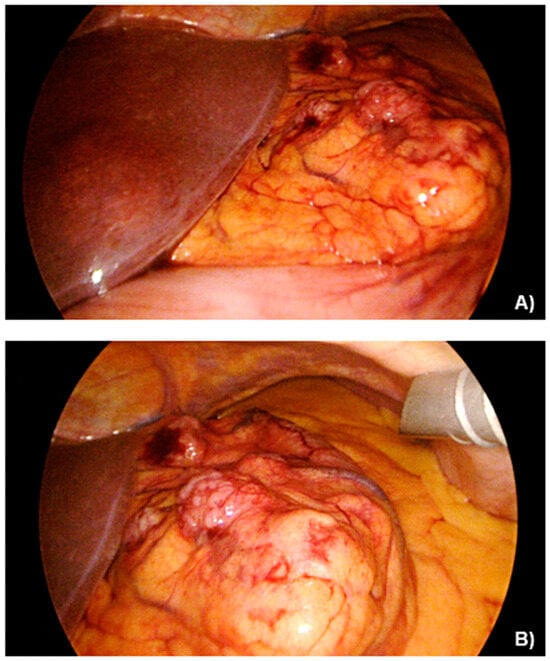

A 69-year-old female, with an unremarkable medical history, underwent an upper-GI endoscopy for progressive dysphagia for solid and liquids. A brittle ulcerous lesion with partial occlusion and signs of recent hemorrhage was detected at the EGJ with expansion to the lesser curvature of the gastric cardia, classified as a Siewert III tumor (Figure 1). The histopathological analysis of the endoscopic biopsies revealed a poorly differentiated invasive adenocarcinoma with HER-2 expression to be negative. The clinical staging included computed tomography (CT) (Figure 2) followed by a staging laparoscopy. Imaging demonstrated a locally advanced tumor (cT4) with a bulky locoregional lymph node packet (cN+) and three liver lesions consistent with hepatic metastases. In front of a possible oligometastatic state of disease, a staging laparoscopy took place to exclude peritoneal seeding and facilitate the application of a percutaneous feeding tube. During laparoscopy, macroscopic peritoneal seeding was excluded, while both the bulky lymph nodes at the lesser curvature and the largest liver metastasis at the left liver lobe could be visually detected (Figure 3). Remarkably, these tumorous lesions demonstrated a soft consistency in palpation with the laparoscopic forceps, which was not expected, as metastatic lesions from adenocarcinoma primary are anticipated to have a solid and hard texture. Therefore, a lymph node biopsy at the lesser curvature of the stomach was contacted in order to exclude different histopathology. The peritoneal cytology after collection of peritoneal washings proved to be negative.

Figure 3. (A,B) Initial exploratory laparoscopy findings, negative for peritoneal seeding, with a visible liver metastatic lesion on the left hepatic lobe.